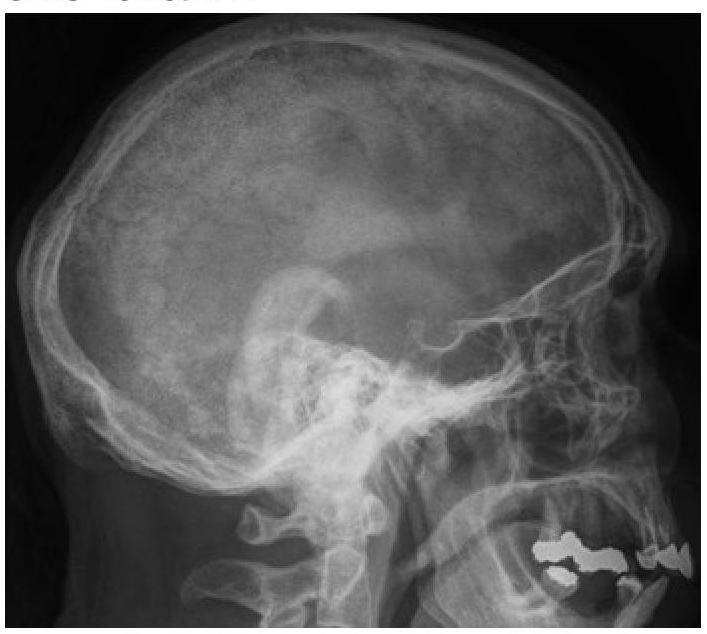

What type of lesions in the skull bones can be identified on this X-ray?

Explanation: ***Paget's disease*** - An X-ray of the skull in Paget's disease typically shows **thickening of the skull vault** and areas of both **osteolysis** and **osteosclerosis**, leading to a characteristic "cotton wool" appearance. - The disease involves abnormal bone remodeling, leading to enlarged and weakened bones susceptible to deformity and fracture. *Multiple myeloma* - On a skull X-ray, multiple myeloma usually presents as multiple, sharply-defined, **"punched-out" lytic lesions** without a sclerotic border. - These lesions reflect areas where malignant plasma cells have destroyed bone, which is distinct from the mixed lytic and sclerotic changes of Paget's disease. *Osteosarcoma* - Osteosarcoma is a **primary bone malignancy** that typically presents as a solitary lesion with a mixture of lytic and sclerotic areas, often with a **sunburst or Codman's triangle** periosteal reaction. - It most commonly affects long bones in younger individuals and is a much less common presentation in the skull compared to other bone conditions. *Osteomyelitis* - Osteomyelitis is an **infection of the bone** that would appear on an X-ray as areas of bone destruction (lysis) and new bone formation (sclerosis), often with **sequestrum** (dead bone) and **involucrum** (new bone formation around the infection). - While it can affect the skull, its imaging features would typically be localized signs of infection rather than the widespread, generalized changes seen in Paget's disease.